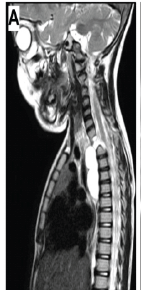

Isolated Anterior Extradural Enterogenous Cyst of the Thoracic Spine Mimicking an Anterior Thoracic Meningocele: A Case Report

Surya Prakash Rao Voleti , Apurve Parameswaran , Ranjith Mahesh Nellore , Raja Shekar Kaitepalli , Vidya Kedarisetti

………………………………p.56-61